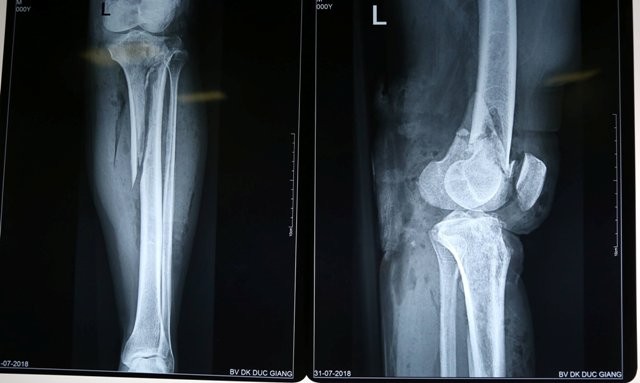

Ngay sau khi tiếp nhận thông tin của bệnh nhân P., các bác sĩ đã nhanh chóng tiến hành sơ cứu, rửa vết thương, cầm máu và chỉ định chụp Xquang và các xét nghiệm cận lâm sàng khác. Kết quả cho thấy bệnh nhân P. bị gãy hở lồi cầu đùi và xương chày trái cùng tổn thương động mạch khoeo.

Sau khi khám và hội chẩn, các bác sĩ quyết định phẫu thuật cấp cứu bằng phương pháp kết hợp xương chầy trái, lồi cầu đùi trái và xử lý tổn thương động mạch khoeo.

Chiều cùng ngày, kíp phẫu thuật do bác sĩ Trần Tuấn Anh – Khoa Chấn thương chỉnh hình cùng bác sĩ Phan Văn Thành – Khoa Ngoại Tổng hợp đã tiến hành phẫu thuật kết hợp xương và xử lý nối động mạch tổn thương cho trường hợp của bệnh nhân P.